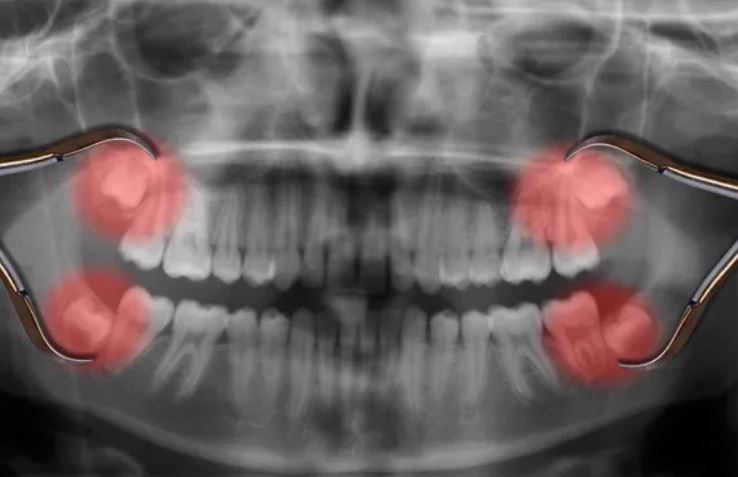

Răng khôn được đánh dấu trên phim chụp X-quang. (Nguồn ảnh: Getty Images)